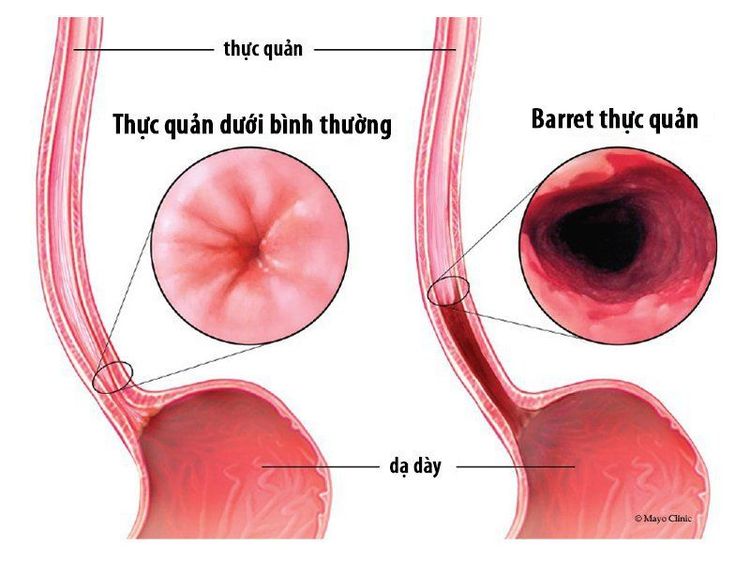

Trào ngược dạ dày thực quản (GERD) là một rối loạn phổ biến với tỷ lệ khoảng 10 - 20% ở thế giới phương Tây. Các biểu hiện lâm sàng của GERD (tức là ợ chua và trào ngược axit) là do trào ngược dịch tiêu hóa trong dạ dày vào thực quản. Lý thuyết hiện tại về cơ chế bệnh sinh của GERD là đa yếu tố liên quan đến cơ vòng thực quản dưới (LES), cơ hoành, sự trung hòa axit thực quản, tiết axit dạ dày, làm rỗng dạ dày và áp lực trong ổ bụng. Định nghĩa Montreal về bệnh trào ngược dạ dày thực quản (GERD) nói rằng GERD xuất hiện khi sự trào ngược của các chất trong dạ dày vào lòng thực quản gây ra các triệu chứng và / hoặc biến chứng. Các biến chứng có thể xảy ra bao gồm viêm thực quản và Barrett thực quản. Trong thực quản Barrett, biểu mô vảy bình thường của thực quản đoạn xa được thay thế bằng biểu mô trụ, làm phát triển biểu mô thực quản dạng cột ở thực quản. Định nghĩa về thực quản Barrett luôn gây tranh cãi và không tồn tại tiêu chí được chấp nhận thống nhất. Định nghĩa phổ biến nhất của Barrett thực quản yêu cầu chuyển sản ruột được xác minh về mặt mô học tại chỗ nối dạ dày-thực quản.

Chỗ nối dạ dày-thực quản (GEJ) là khu vực giải phẫu nơi thực quản đoạn xa nối với dạ dày đoạn gần. Trong điều kiện bình thường, nó nằm ở vị trí ngang với khe hoành. Tuy nhiên, vị trí của GEJ không cố định và di chuyển vài cm trong quá trình nuốt và hít thở. Trong quá trình nuốt, cơ trơn dọc của thực quản co lại làm ngắn thực quản, dẫn đến một thoát vị sinh lý. GEJ sau đó được quay trở lại vị trí ban đầu của nó bằng các cấu trúc hỗ trợ đàn hồi, đặc biệt là bởi màng thực quản - hoành. Khi GEJ cùng với cơ vòng thực quản dưới (LES) và tâm vị dạ dày bị dịch chuyển kéo dài lên trên vào khoang lồng ngực qua cơ hoành, khi đó, tình tràng thoát vị khe hoành sẽ xuất hiện. Các nghiên cứu đã chỉ ra rằng thoát vị khe hoành làm giảm áp lực LES và chức năng cơ vòng của cơ hoành. Sự hiện diện và chiều dài trục của khối thoát vị gián đoạn cũng được chứng minh là tương quan với mức độ nghiêm trọng của GERD.